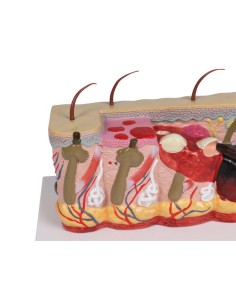

Des modèles anatomiques détaillés pour tous les besoins

Du crâne en 22 parties à verrouillage magnétique aux modèles de colonne vertébrale, des modèles d'articulation aux modèles de cœur, chaque pièce de notre collection est conçue pour une immersion totale dans l'étude de l'anatomie humaine. Nos modèles, réalisés à partir de scans d'os réels, garantissent une expérience tactile authentique et une fidélité de poids presque identique aux originaux.

Des outils pédagogiques innovants pour l'enseignement et la pratique de la médecine

Indispensables aux étudiants comme aux professionnels, nos modèles anatomiques sont des outils pédagogiques qui permettent d'observer les structures anatomiques avec précision, en évitant les dissections ou les études invasives. Ils sont également utiles pour expliquer les pathologies aux patients, ce qui rend la communication plus efficace et permet de gagner un temps précieux.